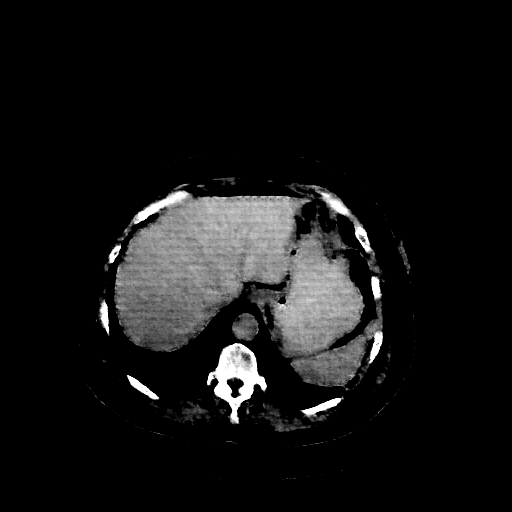

Reconstructed NATIVE CT scan (cycle consistency)

Full window (WL 1023.5, WW 4095 β Low β1024, High +3071)

Actual HU range: [-850.6, 624.8]